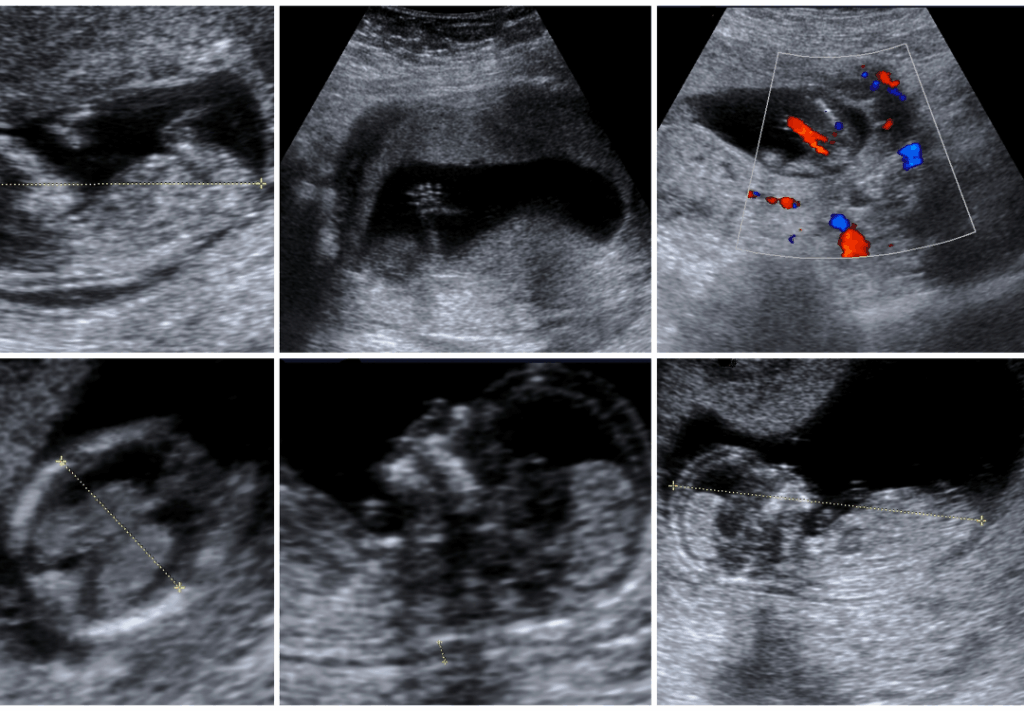

An early anomaly scan (also known as a first-trimester screening) is done between 11–14 weeks to:

Detect structural abnormalities

Assess skull, brain, spine, and limb development

Identify potential chromosomal disorders

A detailed fetal heart scan is recommended between 18–24 weeks to evaluate congenital heart defects (CHDs). Our specialist fetal echocardiography services in Miraj help:

Assess heart structure and function

Detect rhythm abnormalities and defects